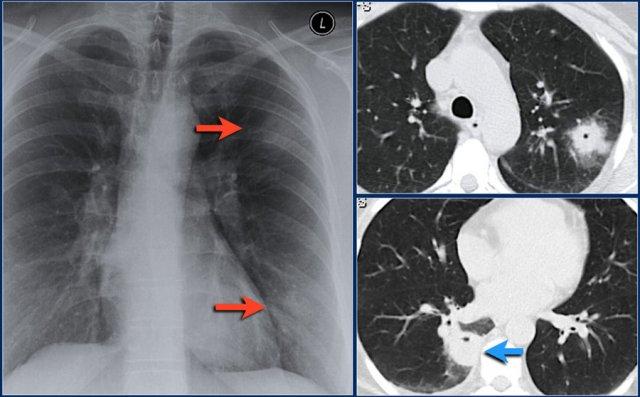

Một dấu hiệu thường gặp trong xẹp thùy trên phổi phải là hiện tượng ‘lều hóa’ cơ hoành (mũi tên xanh dương).

Bệnh nhân này có ung thư phổi vị trí trung tâm kèm di căn ở cả hai phổi (mũi tên đỏ).